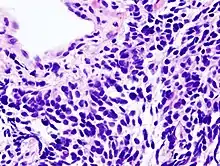

Согласно гистологической классификации рак лёгкого подразделяется на следующие виды:

_by_core_needle_biopsy.jpg.webp)

II. Мелкоклеточный рак

Гистологическая характеристика рака лёгкого достаточно условна, поскольку клиническое течение может сильно различаться даже для опухолей с одинаковой структурой. Медленнее всего растёт дифференцированный плоскоклеточный рак; для недифференцированного рака характерно быстрое течение с обширным метастазированием. Мелкоклеточный рак лёгкого принадлежит к числу самых злокачественных опухолей. Он отличается коротким анамнезом, скрытым и быстрым протеканием, ранним метастазированием, плохим прогнозом.